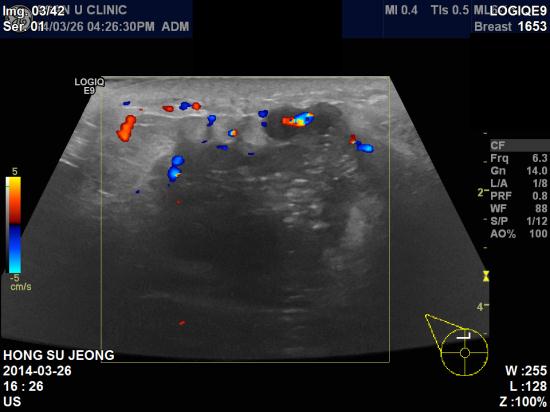

우측유방에 만져지는 멍우리가 있어 내원하신 44세 여자분이십니다.

초음파 검사상 양측유방에 결절이 다발성으로 있었고

가장 의심되는 우측12시방향에 5.15 cm, 좌측1시방향에 0.9 cm 종괴 및 우측겨드랑이의

비대해져있는 림프절 까지 조직검사 및 세포검사를 시행하였습니다.

우측유방의 종괴와 림프절은 침윤성유관암 및 겨드랑이 전이로 진단되었고,

좌측유방은 침윤성소엽암으로 진단되었습니다.